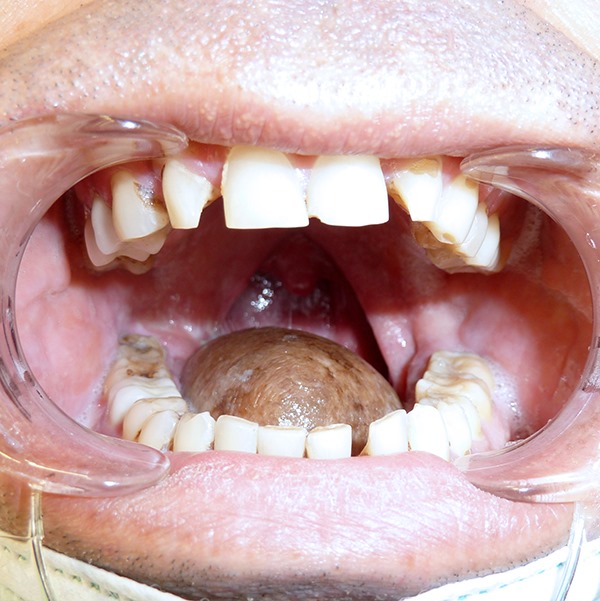

У пациента, 50-летнего мужчины, была обнаружена распространённая опухоль языка. В связи с заболеванием было проведено тотальное удаление языка вместе с опухолью, после чего язык был полностью реконструирован при помощи особого кожно-мышечного васкуляризированного и иннервированного лоскута, сформированного с латеральной поверхности грудной клетки.

Исключительность проведённой впервые в Армении данной операции состоит в том, что удалось не только восстановить структуру языка, но и его подвижность, что стало возможным благодаря сшиванию нервных волокон кожно-мышечного лоскута с сохранившимися нервами языка. Операция длилась 16 часов.

В хирургической оперирующей бригаде были задействованы онколог - специалист области головы и шеи, микрохирурги и челюстно-лицевые хирурги. Перед ними стояли две важные задачи: первая – удаление опухоли возможно более радикальным способом, с целью избежания рецидива, и вторая – восстановление структуры и функций языка (акт глотания, речь).